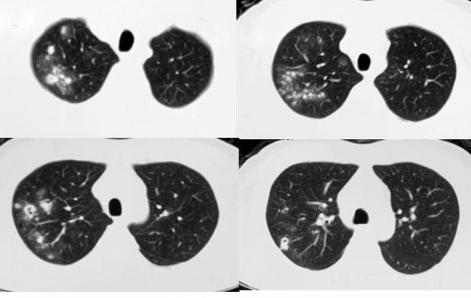

这是一位26岁的姑娘,胸痛半个月,CT发现右肺大片白色实变,周围有少量磨玻璃影,最终确诊肺隐球菌病,经抗真菌治疗后痊愈。

这是一位20岁的医学生,因昏迷住院,CT发现双肺多发白色斑点,像粟粒一样,这种类型比较少见,跟粟粒型肺结核有点像。

后来发现他体内的隐球菌已经播散,还引起了脑部的隐球菌感染,这是造成他昏迷的原因,这种类型有时候是有生命危险的,还好他后来没事了。